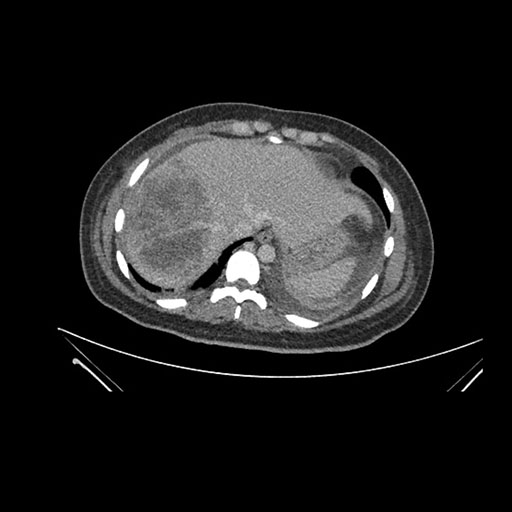

Vasculobiliary injury [M28]

Imaging Analysis

Look through the patient's CT scan to identify any areas of concern for the necessary procedure.

Axial Arterial